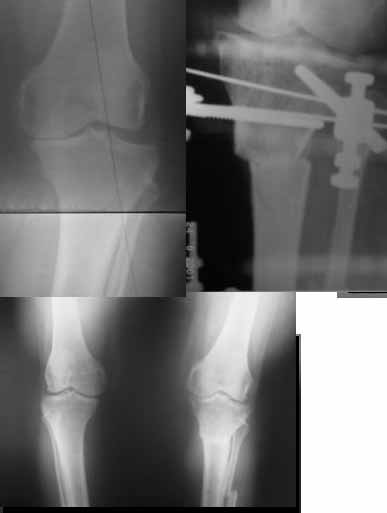

Re: Деформация голеней

Alexander Chelnokov 13 Сентябрь 2005, 23:23

|

a> Совершщенно беспредметный спор. Лучше бы спорили как менее травматично

a> делать остеотомию большеберцовой.

Как уже писал, вчера сделал одну ногу (может, свой плюс будет что не обе- вдвое меньше травма, сразу на костыли встанет, оперированную ножку немного разомнет, тут и вторую заделаем).

Операция была интересной, много полезного опыта приобрел.

Снимки в приложении - фас сравнительный с неоперированной ногой. Жду критики.

Впрос про остеотомию большеберцовой непраздный. Эта получилась при надломе несколько более наклонно, чем я делал (сейчас проблема,

как на второй ноге сделать так же). Вот этот высоящий "зуб" центрального отломка не заменит ли в плане косметики то, что получается при медиализации дистального?

Отправитель: T. Derek V. Cooke 14 Сентябрь 2005, 18:23

Hi Alex:

Nice job!

It is very interesting to me that as you have derotated the tibia you have centred the patella, I think and the prox tibia looks much more anatomic.

The analysis in the attached images is direct, just using the tools.

Tibial tilt is perhaps more than you want but the tibial correction is to 90 (very slight over

correction.

Will need full length views to tell us about the hka but it appears neutral.

Measurements took 4 mins

Derek